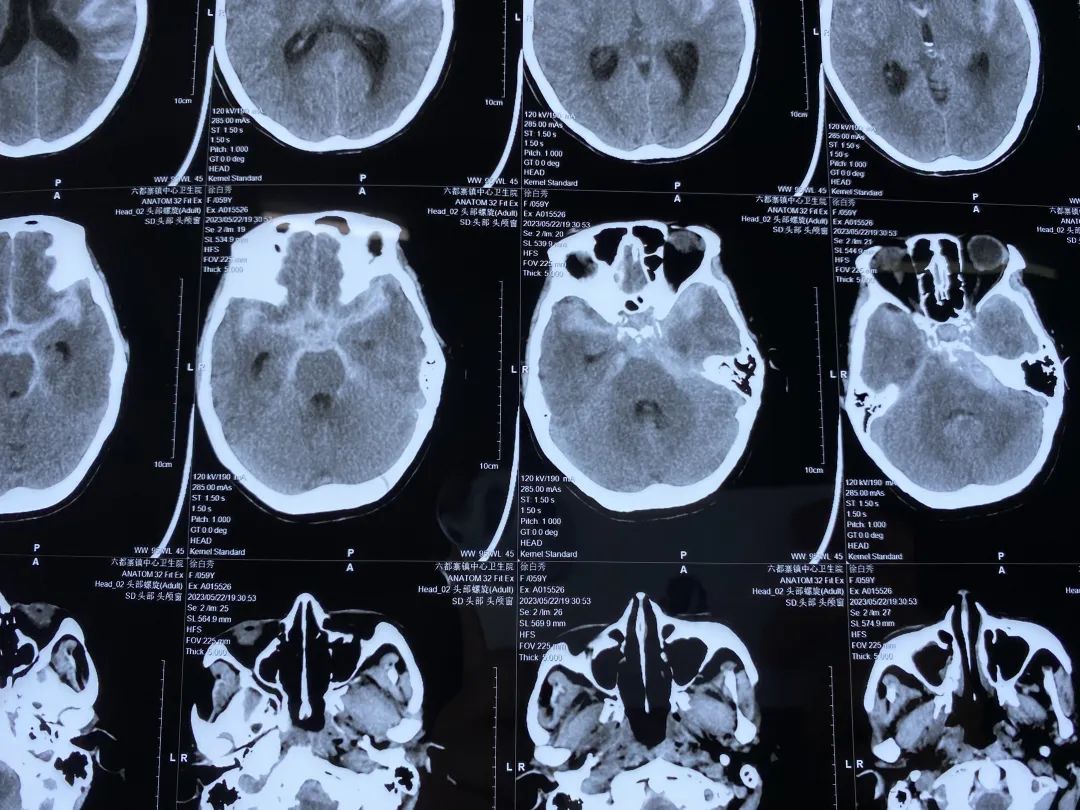

急诊进行抽血、心电图、颅脑CT检查,根据结果排除出血性脑卒中后,患者被诊断为“急性缺血性脑卒中”。